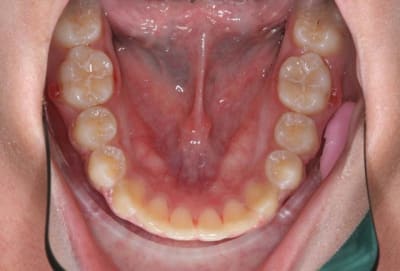

Img 1 xacnga - Eugenol

Img 2 siytdm - Eugenol

Img 3 ituagt - Eugenol

Img 4 r3tw6u - Eugenol

Img 5 z8ak0k - Eugenol

3°) phase

contention

@+ Bjc